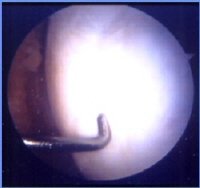

<자가연골배양이식술 후>

연골을 복구하는 방법에는 여러 가지가 있으며 관절내시경으로 시술방법을 결정할 때에 손상된 연골의 크기가 중요하다. 손상된 크기가 2~3cm² 일 경우에는 잘 사용하지 않는 골연골을 채취해 손상된 연골을 복원시켜주는 ‘자가골연골이식술’을 시행할 수 있다. 만약 4cm² 이상으로 연골 손상부위가 클 경우에는 ‘자가연골배양이식술’를 해야 한다.

무릎에서 연골을 소량 채취하여 2~6주 정도 배양하고, 이 배양된 연골을 다시 손상된 부위에 이식하는 방법이다. 0자형 다리와 X자형 다리 같은 부정정렬일 경우에는 다리를 곧게 펴는 절골술을 하고, 인대 손상이 있을 때는 치료를 먼저 한 후 이식한다.

자가골연골이식술이나 자가연골배양이식술이 모든 관절염 환자에게 적용되는 것은 아니다. 말기 관절염 환자는 수술을 하더라도 성공률이 떨어지기 때문에 MRI검사와 그 밖의 세부사항은 전문의와 상담이 필요하다. 이 두 수술은 이식 방법이 조금 다를 뿐 원리는 건강한 연골 세포를 떼어 내 손상 부위에 이식한다는 점에서 동일하다. 시술 후 6개월~1년 정도면 정상적인 운동 능력을 회복할 수 있으며 무엇보다 자신의 관절을 그대로 살릴 수 있다는 것이 장점이다.